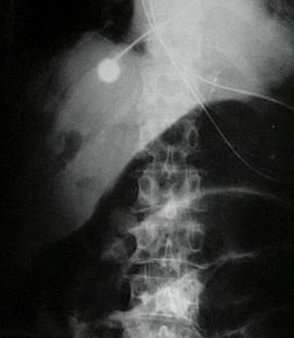

What sign is this?

Cupola sign, the patient is laying down and you see air below the hemidiaphragm